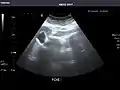

Pancreas

Pancreas: Visualized portions unremarkable.